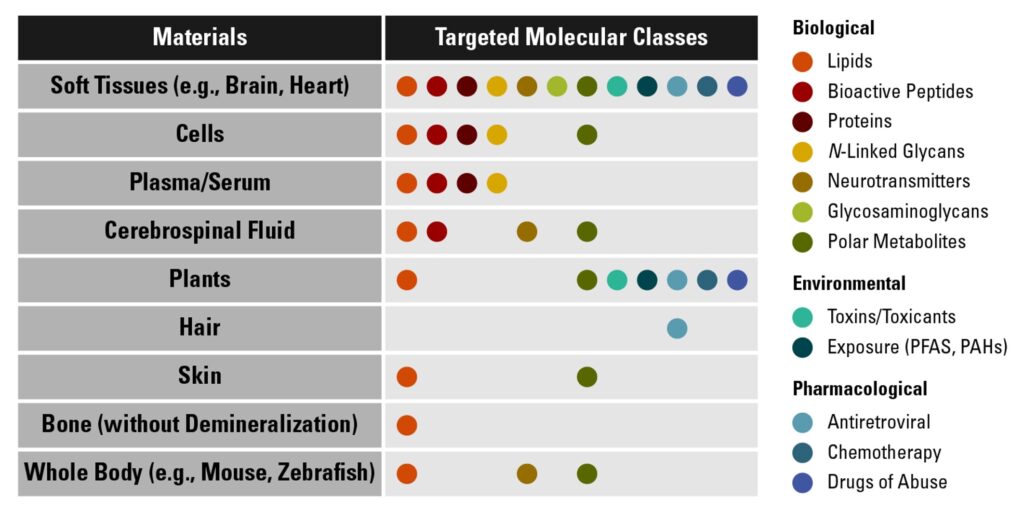

IR-MALDESI is a cold ionization source meaning that it allows the detection of labile molecules (e.g., N-linked glycans containing sialic acids). The method has high salt tolerance, can measure non-flat samples, performs qMSI by spatial calibration curves or VxV, allows for the direct analysis and mass spectrometry imaging of samples, can do ablation-based 3D imaging, parallel reaction monitoring (PRM) imaging, biophysical studies, and does quantitatively sampling. Derivatization or use of secondary lasers is never required for IR-MALDESI mass spectrometry imaging.

The publications below describe the principles, advancements and applications of IR-MALDESI for a diverse range of projects. This strong foundation has been built over the past 20 years as we unraveled the mechanisms, defined how “soft” the method is, demonstrated 2D and 3D imaging, created novel approaches for matrix applications, demonstrated transmission-mode IR-MALDESI, carried out imaging of non-flat samples using a confocal aberration probe, quantitative MSI (qMSI) using both spatial calibration curves as well as voxel-by-voxel strategies, and countless examples of the impact to biological systems.